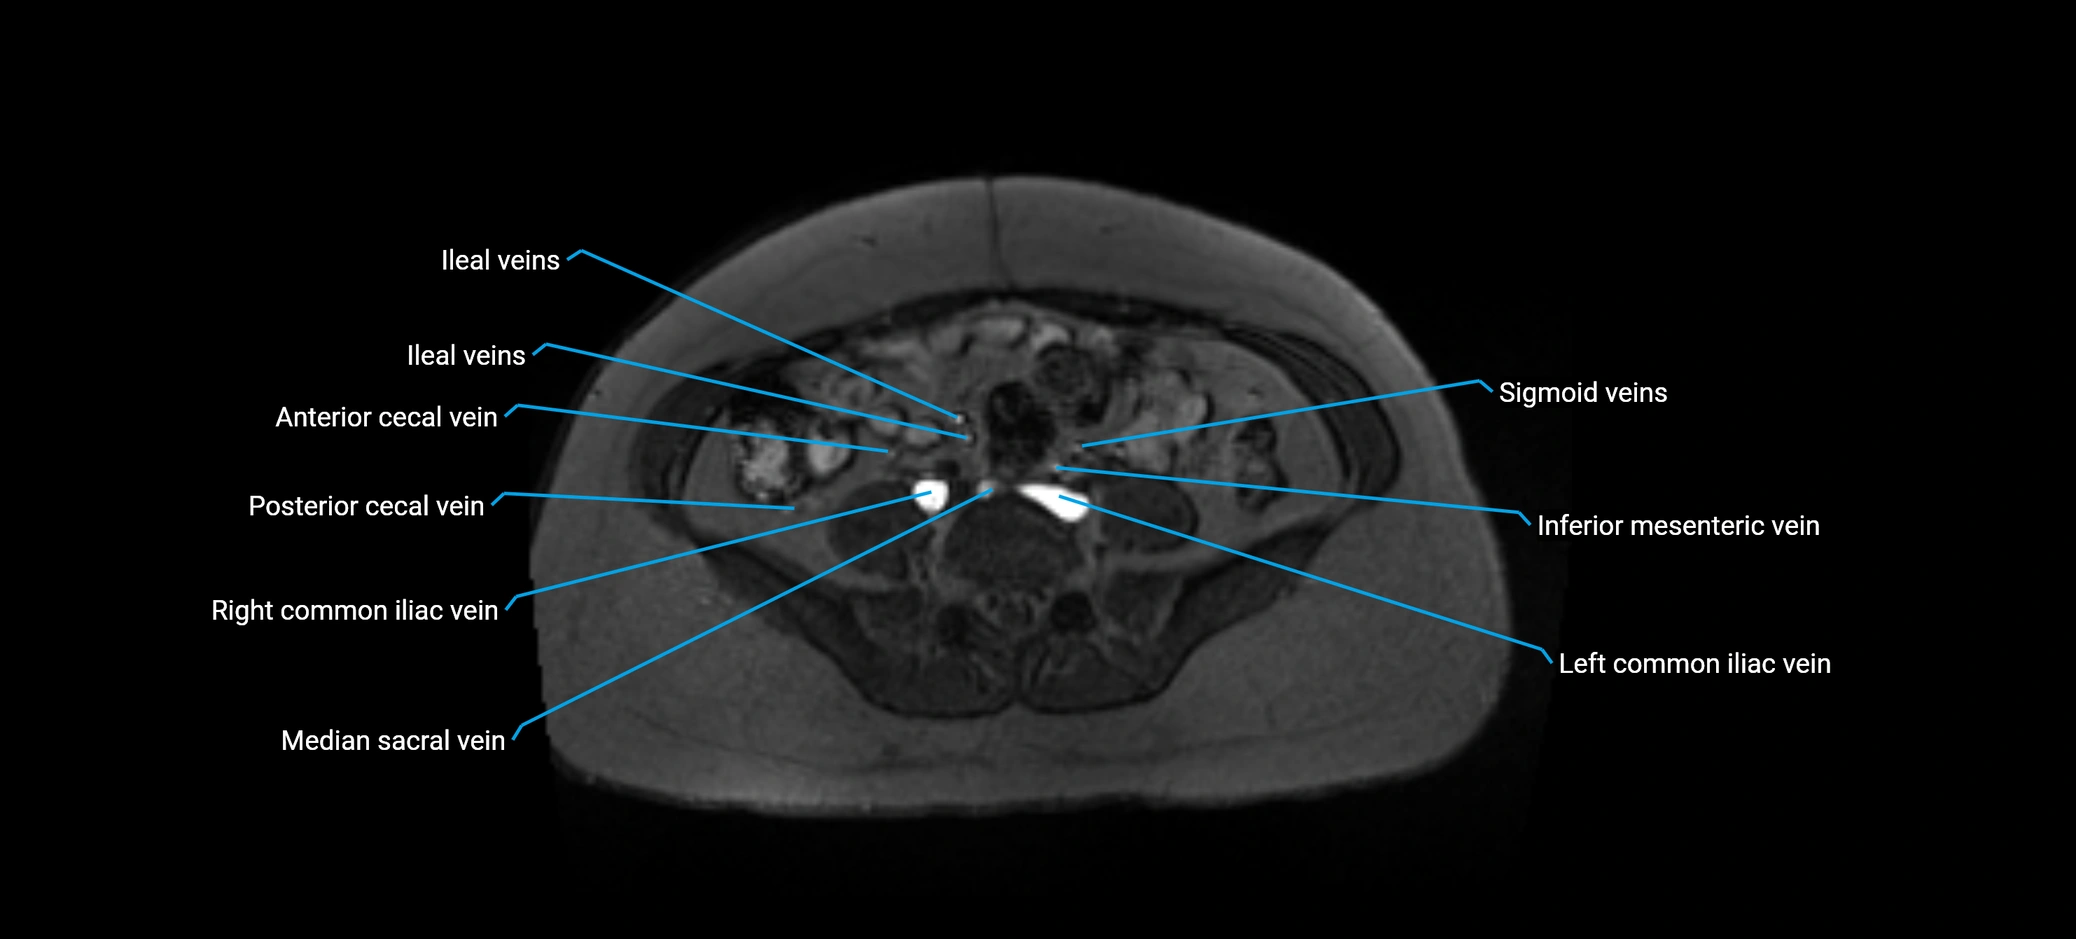

MRI image

image